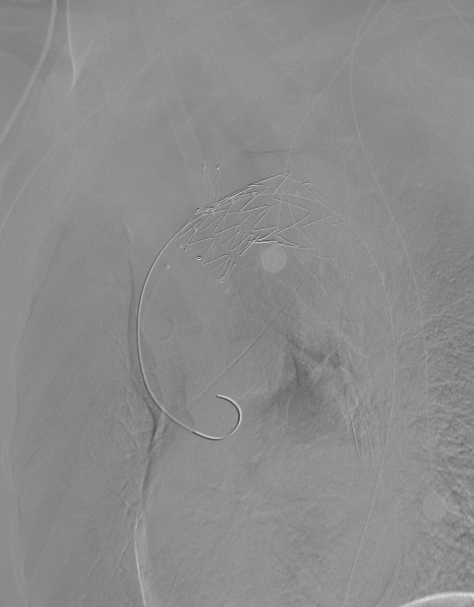

动脉长鞘怎么置入【弓部重建直通车】真腔难觅,另辟蹊径|潍坊市人民医院血管外科运用Castor®支架结合长鞘建立导丝通路治疗主动脉夹层两例_https://www.jmylbn.com_新闻资讯_第8张

与长鞘并行导入造影导管

动脉长鞘怎么置入【弓部重建直通车】真腔难觅,另辟蹊径|潍坊市人民医院血管外科运用Castor®支架结合长鞘建立导丝通路治疗主动脉夹层两例_https://www.jmylbn.com_新闻资讯_第9张

术前造影

1、穿刺患者左肱动脉与右股动脉,并在左肱动脉置入5F的穿刺鞘后,导入软导丝,从右股动脉导入7F长鞘至降主动脉,交换超硬导丝与分支导丝并导入造影导管进行造影;